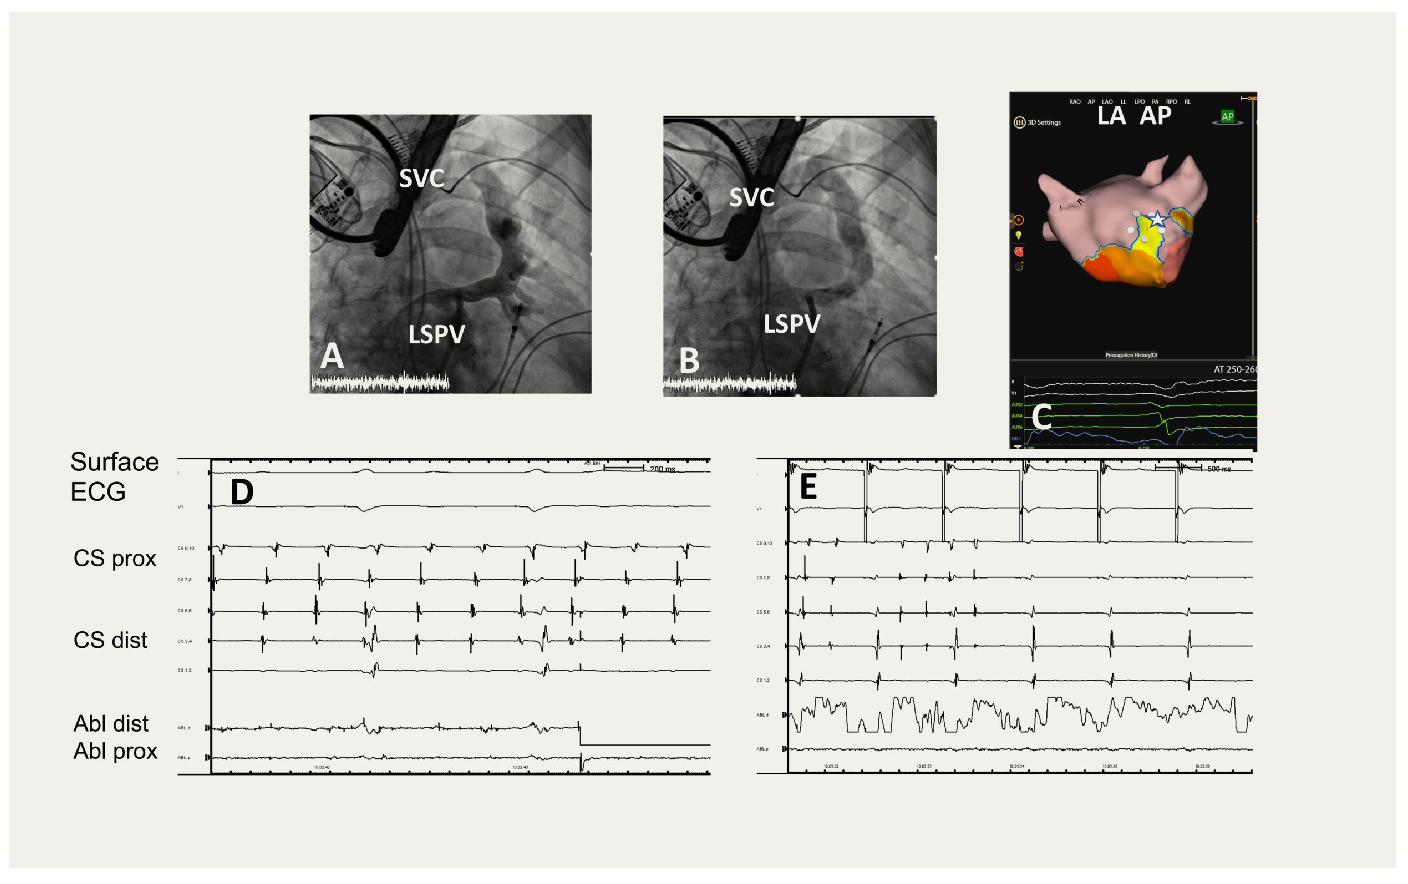

At the age of 51 years, the patient had a transient ischemic attack. Because of symptomatic atrial arrhythmia, an electrophysiology procedure with AcQMap® from Acutus Medical was performed. During contrast injection into the left superior pulmonary vein (LSPV), an abnormal vertical vein connection to the brachiocephalic and superior caval vein (SCV) was found (Figure 3A,B).

The pulmonary veins had no activity during an irregular atrial arrhythmia of varying cycle length between 230 and 260 ms with very low amplitudes on surface electrocardiogram (ECG) (Figure 3D). Beat-to-beat atrial mapping with the Acutus system showed a focal origin of about 0.5 cm diameter at the anteroseptal left atrium (Figure 3C). During RFA conversion to sinus rhythm was observed (Figure 3E). No further atrial arrhythmia could be induced with pacing down to 250 ms cycle length. During follow up of 1.5 years, the patient remained free of relevant atrial arrhythmia (atrial fibrillation burden <0.7% in the PM interrogation) (Figure 4). An upgrade to an ICD was done in 2021, when the Lamin mutation had been diagnosed. The vertical vein connection was closed percutaneously with an Amplatzer™ cardiac plug.

Figure 3. Electrophysiology procedure of patient B showing a vertical vein connection and an atrial arrhythmia from the left atrial septum. A) and B) Two consecutive images during contrast injection into the left superior pulmonary vein (LSPV) draining into the superior caval vein (SVC). C) Mapping of atrial arrhythmia with AcQMap® showing the target site at the left atrial septum in AP view with a white star. D) Surface electrocardiogram (ECG) showing the Initial arrhythmia with concentric coronary sinus (CS) activation and termination during radiofrequency ablation at site of white star. E) Non-inducibility during atrial pacing down to atrial effective refractory period of 250 ms.